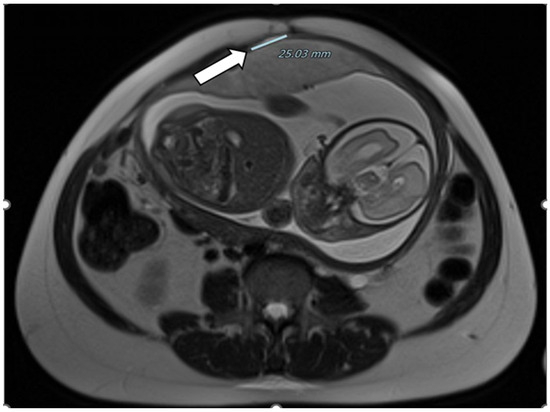

| Zermano S. et al. | 2024 | Yes | Yes | Yes | 24 5/7 | ||

| Zermano S. et al. | 2024 | 29 1/7 | No | Yes | Yes | Yes | |